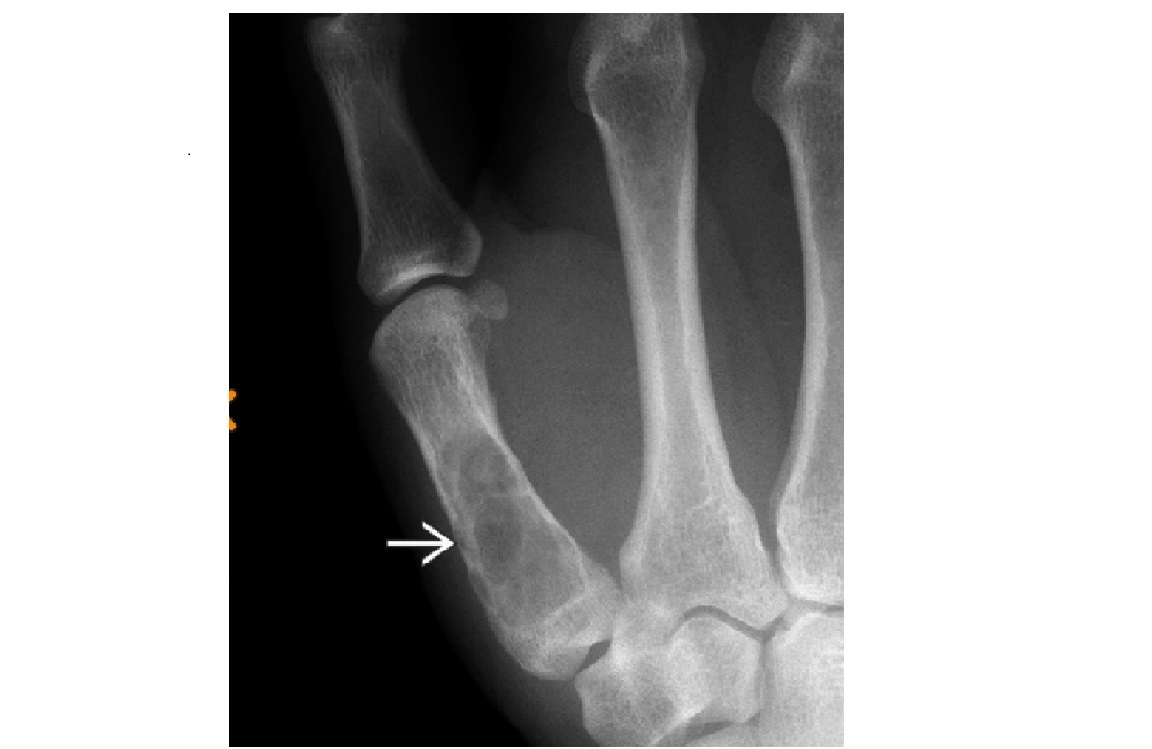

What is bennetts fracture?

A

Fracture base of the first metacarpal

Pull of the abductor pollicus longus (APL tendon causes dorsolateral dislocation

Nb a comminuted # base of 1st metacarpal = ROLANDO